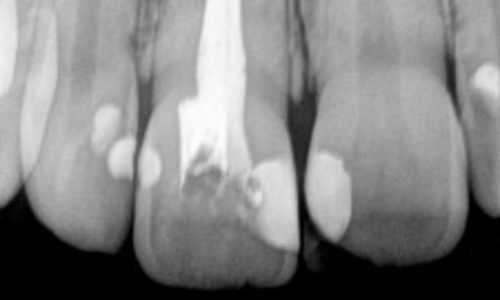

Welcome to Dhanusha Dental Clinic, where your oral health is our priority. Our modern facility boasts RVG X-ray for precise diagnostics, an Endo Motor and APEX LOCATOR for efficient root canal treatments, and five dental chairs to accommodate multiple patients comfortably. With a team of five specialized doctors and a well-trained staff, we offer expertise in general dentistry, orthodontics, periodontics, prosthodontics, and oral surgery. Utilizing dental loupes for precision, we maintain high sterilize standards for a clean environment. Our emergency readiness includes an oxygen cylinder and well-stocked emergency kits. At Dhanusha Dental Clinic, experience top-notch care with cutting-edge technology and a commitment to your well-being.